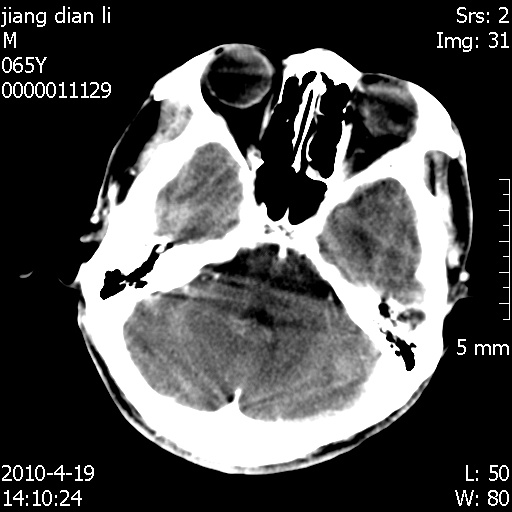

老年男性,突发左下肢无力1天,其余有价值的检查都没有。平扫ct值大约60hu,增强后ct值没什么改变,请大家讨论一下这个病例是什么?说明诊断理由。

左小脑、右大脑顶叶多发圆形高密度病灶,其周环状低密度影。考虑多发脑出血。隔期观察。